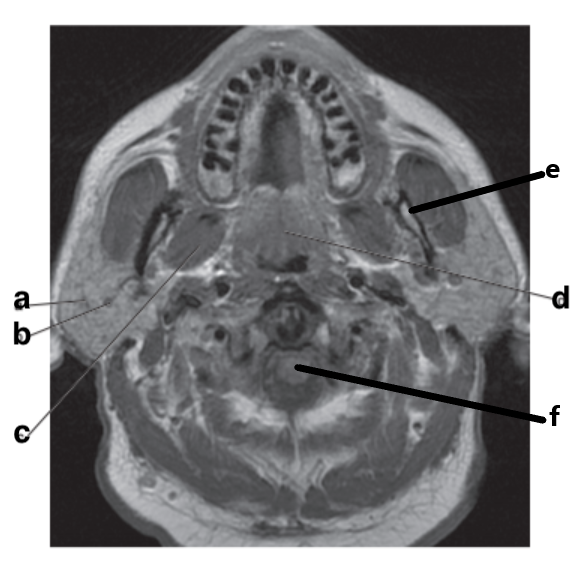

What is letter e?

Subclavian artery

What is letter f?

Vertebral artery

What is letter b?

Left ventricle

Mandible

Parotid gland

What is letter a?

What is letter d?

Internal carotid artery

What is letter c?

Submandibular gland